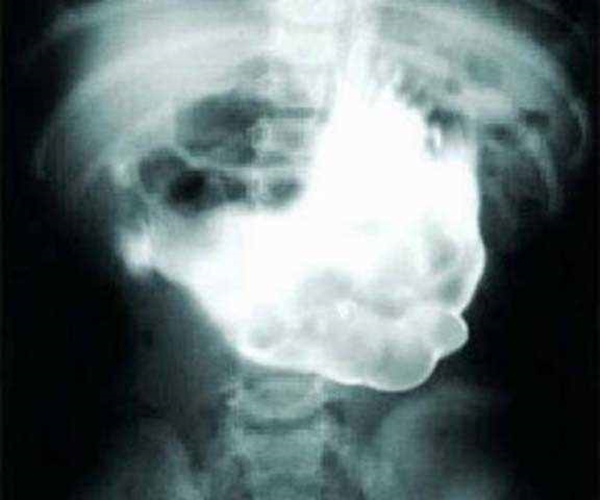

#10

Foto - 36 yıl sonra midesinden kardeşi çıktı!

Kocaman bir böbrek taşı - Böbrek taşı düşürmek doğumla eş değer bir acı olarak bilinir. ufacık olanları bile damarları tıkayabilir ve enfeksiyona sebep olabilir. Bu adamın böbreğinden çıkan, yaklaşık 1.1 kilogram ağırlığındaki böbrek taşı neler çektirmiştir, bir düşünün. Böbrek taşını düşürmenin tek yolu bol su içmektir ama, bu taşı düşürmek için dünyadaki tüm sular yetersiz kalır. Bu yüzden taş ameliyat yoluyla alındı.